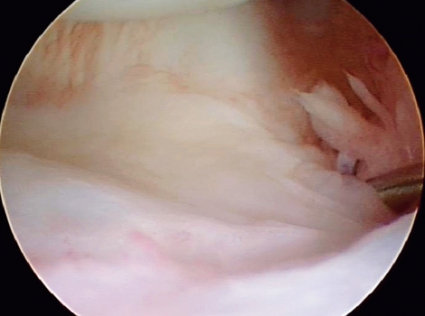

Akuta skafolunära skador fixeras med stift: ett mellan scaphoideum och lunatum och ett mellan scaphoideum och capitatum. Stiftningen görs med fördel artroskopiassisterad så att man ser att stiften hamnar rätt och att det skafolunära intervallet sluts adekvat. Stiften bör sitta kvar i ca 8 veckor medan patienten är gipsad. Om stiftningen görs i akut skede blir slutresultat vanligen gott, men med viss stelhet [1].

• Artroskopifynd: Är haktestet positivt, dvs går disken att lyfta upp med haken underifrån? I så fall tyder det på att det djupa foveala TFCC-fästet är skadat. Är typen av skada sådan att den tillåter reinsertion eller inte?

Vid total TFCC-skada utförs reinsertion artroskopiskt eller öppet med numera väsentligen likartade kliniska resultat [7]. Reoperationsfrekvensen är ca 15–20 procent, men i övriga fall är resultaten generellt sett goda. Risken för reoperation är något större för kvinnor och markant ökad vid ulna+. Samtidig ulnaförkortning ska då absolut övervägas vid ulna+. Ulnaförkortning kan också vara ett bra operationsalternativ vid instabilitet i distala radioulnarleden enbart i neutralläge, vilket talar för en isolerad ulnokarpal ligamentskada.